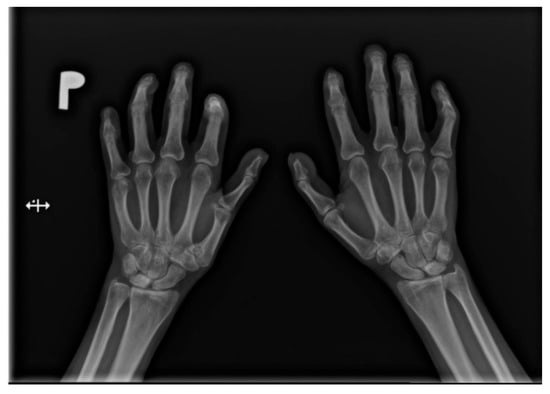

Hands are the most characteristic location of lesions in SSc. Articular symptoms are seen in 10–60% of patients at the time of diagnosis. Features allowing to distinguish changes caused by scleroderma from symptoms of other diseases are predominantly acro-osteolysis, calcifications, and soft-tissue thinning, which are all visible on radiographs [13]. According to the latest research, acro-osteolysis (Figure 1 and Figure 2) is seen in about 16% of patients [14]. The distinctive ‘sharpened pencil’ sign is caused by resorption of the terminal tuft of distal phalanges; this symptom is usually more pronounced on the palmar surface of phalanges. A correlation between acro-osteolysis and digital ulcerations was observed. The less common locations where bone resorption might be seen in SSc patients include medial parts of the ribs, distal end of the radial and ulnar bones, clavicle, and mandibulum [15,16]. Although acro-osteolysis is a common finding in SSc, a number of other pathological entities might be also associated with this symptom—including rheumatological disorders, psoriatic arthritis, hyperparathyroidism, and thermal injuries [17,18].

Figure 1.

A-P view of the hand radiograph in a patient with systemic sclerosis shows acro-osteolysis especially expressed in the distal phalanx of the second finger of the left hand and in the distal phalanx of the second finger of the right hand.

Figure 2.

A-P view of the hand radiograph in a patient with systemic sclerosis shows acro-osteolysis of the distal phalanx of the first, second, third, and fourth fingers of both hands. Additionally, small joint contractures and areas of calcinosis in the fingertips are visible.

The soft-tissue thinning is visible and may be objectively evaluated on a hand radiograph—by comparing the thickness of tissue of the fingertip and at the basis of the distal phalanx. A ratio below 0.2 is an unambiguous symptom of peripheral soft tissue thinning. Moreover, repeated calculation of this parameter might be useful in the monitoring of the disease progression [19].

Soft-tissue calcifications are observed in about 46% of patients [20]. Both subcutaneous and periarticular locations are possible. Periarticular calcifications were reported not only in typical peripheral regions (e.g., in the hand), but also in less frequent areas, such as the paraspinal site, including even the spinal canal itself, with a possibility of its narrowing [15].